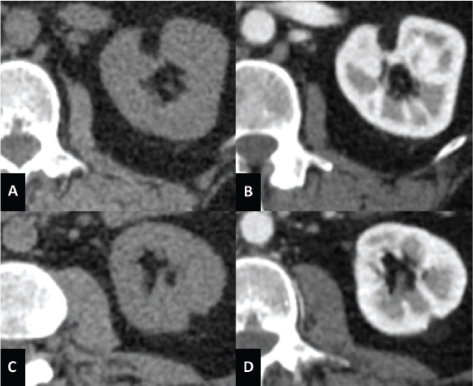

On magnetic resonance imaging (MRI), it appears isointense compared with fat on T1-weighted images; moreover, with the use of in-phase and opposed-phase imaging, AMLs with predominant adipose component show the characteristic India ink artifact that appears at the interface between the lesion and the normal renal parenchyma on opposed-phase T1-weighted images. In T2-weighted images, however, the intensity can be variable, depending on the amount of adipose tissue present in the lesion, resulting homogeneously high in AMLs with a higher adipose component (Figure 2) (5154).

Fig 2

Figure 2. MRI axial scan of the abdomen shows two AMLs of the left kidney. (A) Opposed-phase shows the characteristic India ink artifact of the AMLs. (B) AMLs appear hyperintense on T2-weighted images and (C) hypointense on T2-weighted images with fat suppression. (D) T1-weighted image with fat suppression shows contrast enhancement of the AMLs.